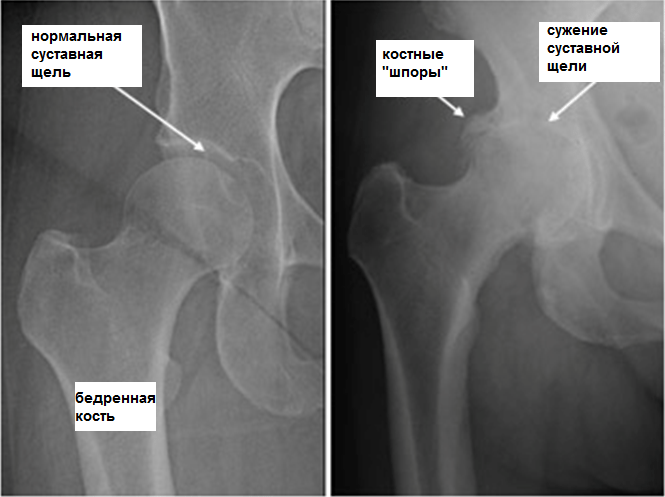

Коксартроз

Причиной развития такого заболевания является изменения структуры хрящевой ткани, нарушение питания и кровоснабжения тканей. Спровоцировать проблему может аномальное строение скелета, нарушение обменных процессов в организме, слишком большая масса тела. Симптоматика при этом такова: изначально появляется стартовая боль, которая имеет умеренную интенсивность. Однако со временем дискомфорт и неприятные ощущения усиливаются.

Если на 1 стадии сначала они появляются только при движении, то с развитием заболевания болевой синдром не проходит даже во время покоя. На второй и третьей стадиях развития патологии боль не исчезает даже ночью. Объем движения уменьшается с каждым днем. Естественно, необходимо обязательно проводить лечение этой болезни. Если она уже запущена, то на 4 стадии патологии придется делать операцию. Дело в том, что болезнь способствует деформации тазобедренного сустава. При данном заболевании болевые ощущения могут появляться даже в боку, паху и колене. Мышцы при коксартрозе сильно напрягаются, больной начинает хромать.

- рентгенография. Это основное исследование, которое позволяет увидеть состояние костной ткани;